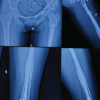

A 16-years-old male medically with a history of road traffic accident sustained isolated close left acetabulum fracture. Examination where was tenderness, restricted range of motion due pain, cannot bear weight, and distal neurovascular intact of left hip joint otherwise upper extremity examination unremarkable. X-ray shows associated both column acetabular fractures with central subluxation (Fig. 1).

Pan CT done showed an isolated left acetabulum fracture with segmented fracture of the left superior pubic rami fracture, acetabulum dissociated from the iliac bone and there is central subluxation (Fig. 2-7).

Second day of admission, emergency treatment was done for the patient in the form of left distal femur skeletal traction to reduce central dislocation and enhance the fracture complexity. Post-operation, the patient was fine, and distal neurovascular examination intact left the lower limb intact. The patient underwent ORIF on the 6th day of the trauma. Patient positioning was supine position on radiolucent Jackson table with both arms on 90° shoulder abduction over the arm support. After patient intubation, anesthesia physician inserted arterial line in the left upper extremity for better monitoring of the patient condition and Hgb assessment. After antibiotics and prepping with draping the patient, we proceeded with open reduction and internal fixation through a modified Stoppa approach with a lateral window. Fixation was done with suprapectineal Stryker plate, symphyseal recone plate, 2.7 mini fragment plate, and two posterior column screws (Fig. 8-11).